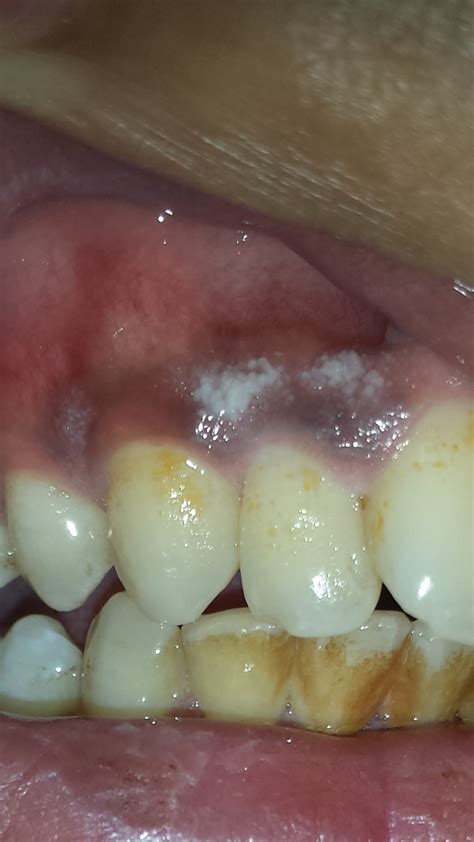

Discover the common causes of white spots in the gums, ranging from canker sores to oral thrush and leukoplakia. Learn when these painless or painful patches require professional dental care and explore effective treatment options to restore your oral health. Understand the warning signs and symptoms to keep your mouth healthy and disease-free.

Read full article: White Spots In The Gums